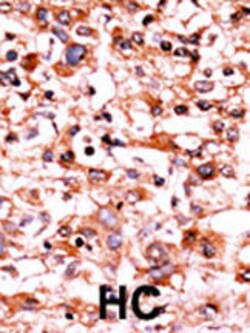

Invitrogen™ Phospho-CDK1 (Ser39) Polyclonal Antibody

| Applications | Dot Blot, Immunohistochemistry (Paraffin), Western Blot |